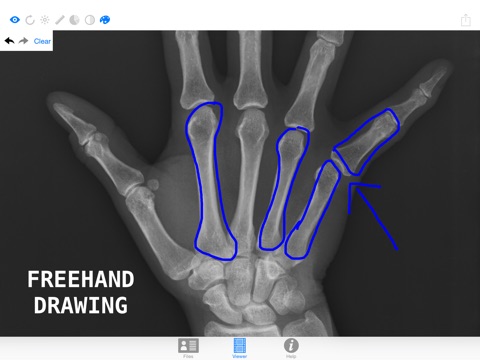

3. Change contrast and brightness or even invert colors. The level of detail you can obtain is higher than any printed traditional x-ray. Dont let the doctor get all the fun, you can get your pro x-ray image too!